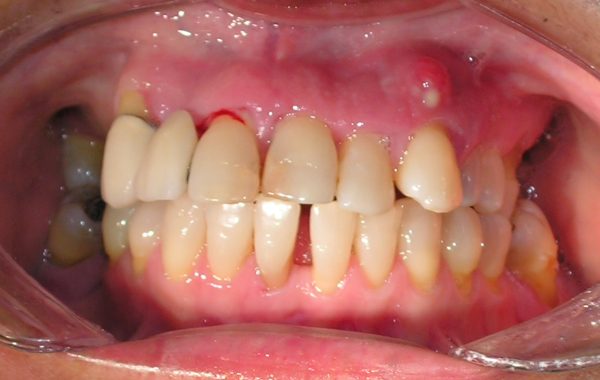

Paciente #6

Aquí tenemos otro caso de una paciente de 65 años de edad a la cual se le colocaron 12 implantes. Seis de ellos en el maxilar para soportar una dentadura sin paladar y los otros seis en las partes posteriores de la mandíbula para colocarle prótesis fijas cementadas.

Prótesis removibles mal ajustadas y antiestéticas

Radiografía con los 12 implantes colocados